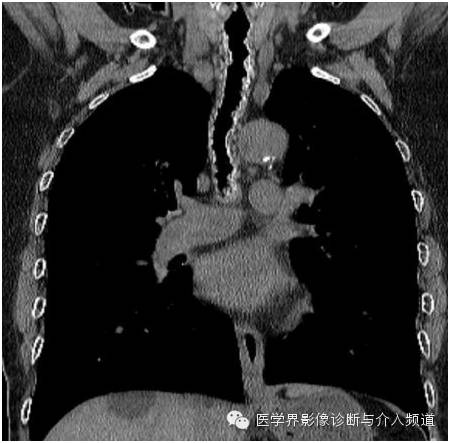

胸部CT平扫显示主支气管前壁及两侧壁可见多个钙化及未钙化的结节,后壁未见异常病变。支气管镜检如上图。

CT主要表现为在气管支气管前壁和侧壁黏膜下散在或多发分布斑点钙化状小突起,突向管腔,大多数突起直径在 1~3 mm,但有的结节较大,达到10 mm。一般黏膜下高密度钙化状影和气管环不连接。

TO病变严重时,气管壁弥漫增厚,管壁塌陷,管腔缩小。当病变发生在叶支气管或段支气管时,常导致管腔狭窄,加上黏液栓塞,极易引起肺不张。病变主要发生在气管中、下段的前、侧壁,后壁一般不累及。但也有文献报道后壁也可见,主要发生在较严重的病例。

总之,TO是一种罕见疾病,临床症状不典型,因此对于怀疑TO患者,胸部CT扫描是非常必要的检查,如出现气管前壁及两侧壁黏膜不规则钙化,后壁正常,需高度怀疑TO,进一步的支气管镜和组织病理学检查可明确诊断。